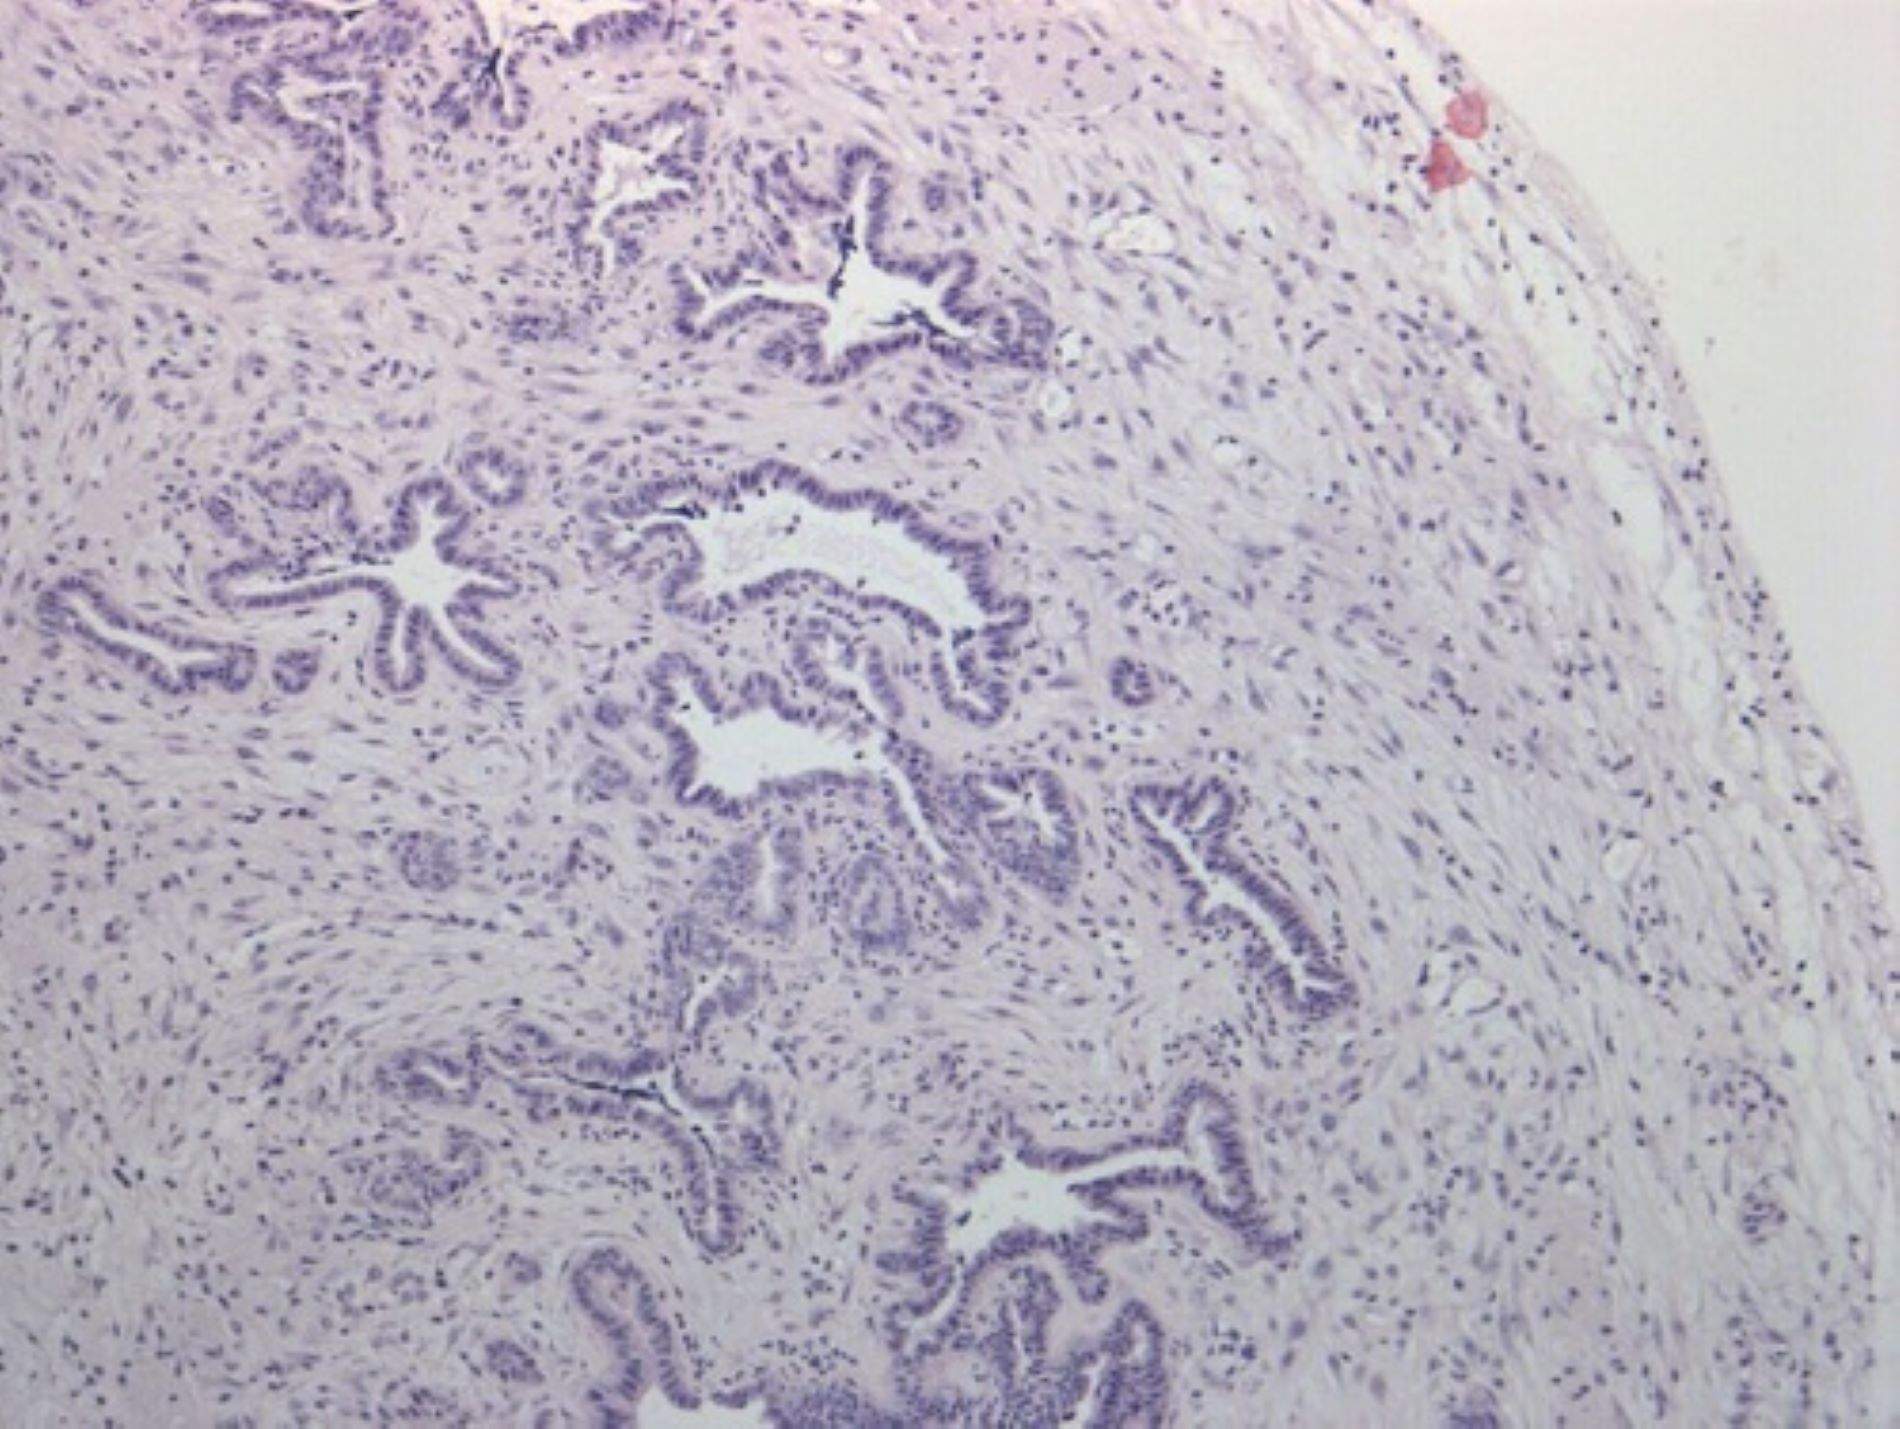

Un estudio demuestra el papel de la proteína Galectina-1 en el núcleo de las células que rodean el tumor

Martes, 15 de abril de 2025 - 18:25